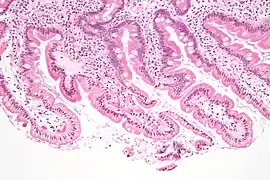

Sección de duodeno de gato

Duodeno con depósito de amiloide en lámina propia

Micrografía mostrando giardiasis en biopsia duodenal.